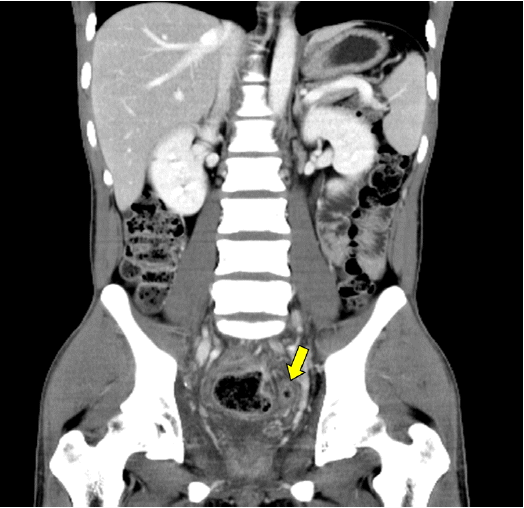

방사선학적 소견: 단순 복부 방사선 사진에서 특이소견 없었고, 복부 전산화단층촬영에서 직장벽이 두꺼워져 있었으며 직장-S상결장접합부에 협착이 있으면서 그 위로 장이 확장되어 있었다. 직장-S상결장접합부 하부로는 염증소견이 있으면서 조영증강된 장벽(target sign)이 보였다(Fig. 1). 그밖에 대동맥주위 림프절이 커져 있었으며 다른 특이소견은 관찰되지 않았다.

Figure 1.

Abdomen and pelvic computed tomography (CT) [coronal view] shows dilation of the proximal rectosigmoid junction and the target sign, which reflects the near-total obstruction caused by the inflamed bowel (arrow).